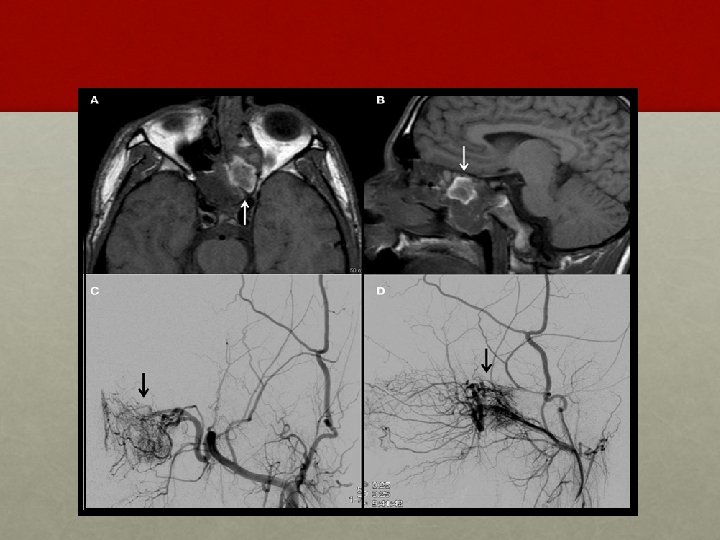

INVESTIGATION: • Contrast enhanced CT scan of nose and PNS • Holman Miller sign/ Antral sign • MRI – soft tissue extent

• ANGIOGRAPHY: • Carotid or four vessel angiography - vascular nature of the tumour, its feeding vessels and extension of the tumour. • In addition during angiography embolization of the feeding vessel with gelfoam can be done pre-operatively to shrink the tumour and reduce bleeding during surgery. • BIOPSY: controversial